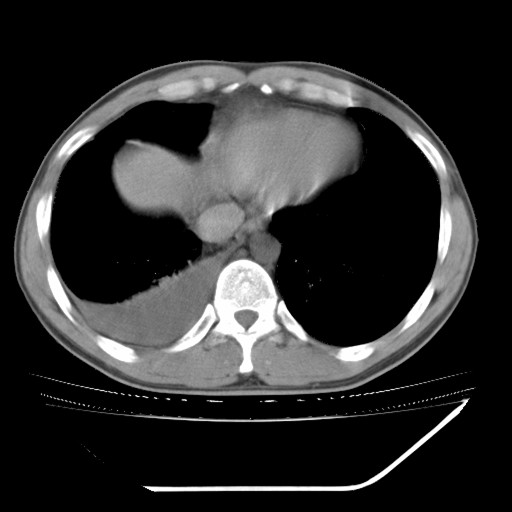

男,32岁,多年前右上肺结核,近期胸部不适,ct检查次序如上,上传主要层面,纵隔未见明显肿大淋巴结。

本人初次(2008年12月20日ct片)诊断为右上肺结核伴右侧胸水!保守治疗后,遂复查ct胸水逐渐减少!最后(2009年05月18日)诊断为右上肺结核,右侧胸水吸收后伴包裹形成!从逐次ct检查上看,胸水吸收好转,只是从2009年05月18日ct片看到一个胸膜结节。临床医生及某肿瘤医院认为2009年05月18日ct片,右后胸壁结节,考虑为胸膜肿瘤!

本人还是倾向于右后胸壁的局限性包裹,胸膜结节密度不均匀,其内可见低密度区,考虑是由胸水吸收后胸膜增厚、粘连及周围肺组织包裹形成的征象;不倾向于胸膜肿瘤的诊断。

右肺上叶继发性肺结核,右侧胸腔积液部分包裹,右侧胸膜肥厚粘连。

支持 右肺上叶继发性肺结核,右侧胸腔积液部分包裹,右侧胸膜肥厚粘连;右下胸后壁胸膜结节,多为结核所致。